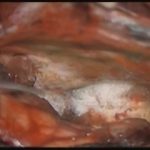

術中写真

摘出 中

摘出 後